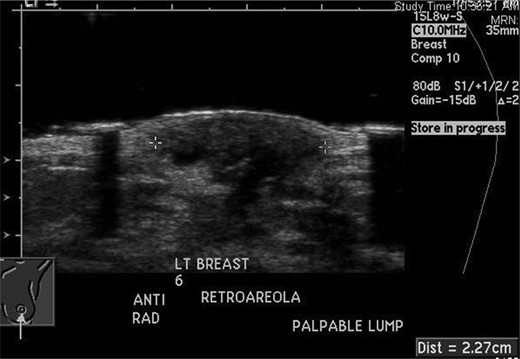

A 20-year-old female with a history of neurofibromatosis, and left breast supernumerary nipple excision presented to her primary care physician, after noticing a lump in her left breast at the site of her previous surgical scar after accidentally bumping her breast in January 2012. Her primary care physician then referred her to the breast surgery clinic at St. Barnabas Hospital. She was seen and examined at the breast clinic, where a palpable firm 1 × 1 cm mass was identified at the 6 O'clock position. She denied any nipple discharge. The decision was made to obtain an ultrasound (seen in Fig. 1) with close follow-up in the breast surgery clinic.

She returned to clinic later in January after the ultrasound, which revealed a 1.4 × 0.9 × 1.8 cm fluid collection at the 6 O'clock position most likely representing a hematoma; BIRADS #3 likely benign recommend short-term follow-up. She was scheduled for a repeat ultrasound in April 2012 with follow-up in breast clinic following the ultrasound. Repeat ultrasound (seen in Fig. 2) revealed a stable fluid collection measuring 1.5 × 1.2 × 2.2 cm, once again BIRADS #3 likely benign recommend short-term follow-up with the breast surgeon. She was seen in clinic following the ultrasound in April and reported decreasing pain and no nipple discharge, she was given a 1-month follow-up appointment.